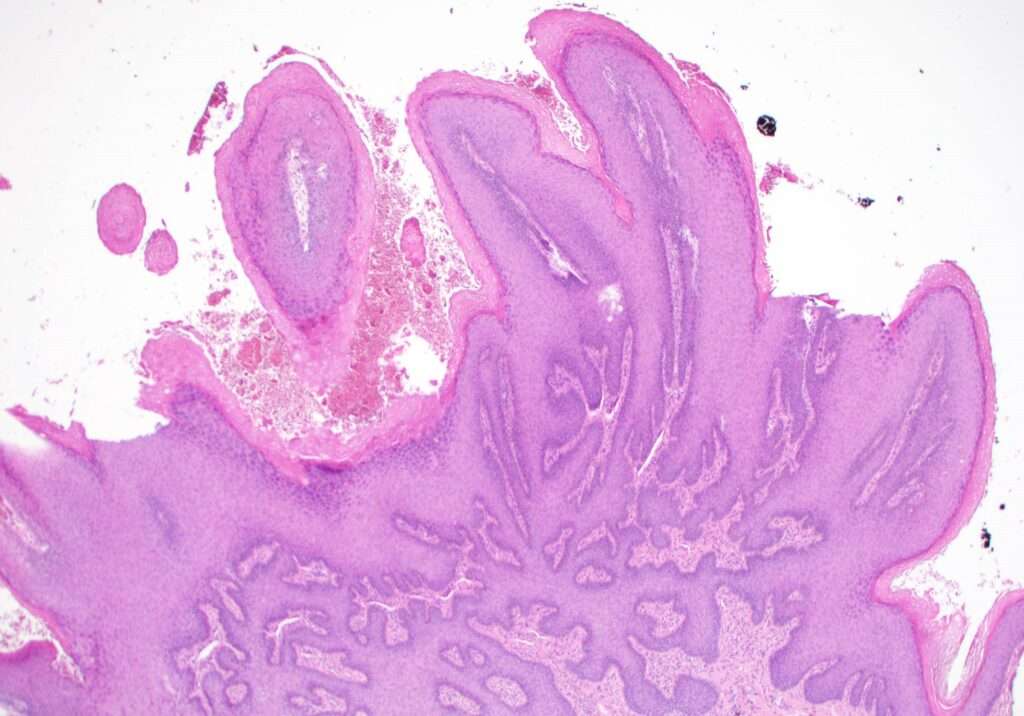

El condiloma acuminado, también conocido como verrugas genitales, es una manifestación clínica de una infección viral causada por diferentes tipos del virus del papiloma humano (VPH), particularmente los tipos 6 y 11, que son responsables del 90% de los casos de verrugas genitales. Estas lesiones, que se localizan principalmente en la vulva, el área perianal, las paredes vaginales o el cérvix, se caracterizan por el crecimiento anómalo de la piel y las membranas mucosas, presentando una apariencia de verrugas que pueden variar en tamaño y forma, y a menudo se describen como crecimientos similares a coliflor.

Las lesiones vulvares pueden manifestarse de manera evidente como verrugas prominentes, o en algunos casos, la presencia de las mismas solo se puede confirmar mediante una biopsia de los tejidos sospechosos, debido a que no siempre tienen una apariencia típica. Las lesiones vaginales, por otro lado, pueden presentar un engrosamiento difuso de los tejidos o adoptar una apariencia en forma de piedra de adoquinado, lo que también puede generar dudas diagnósticas y requerir un análisis más exhaustivo.